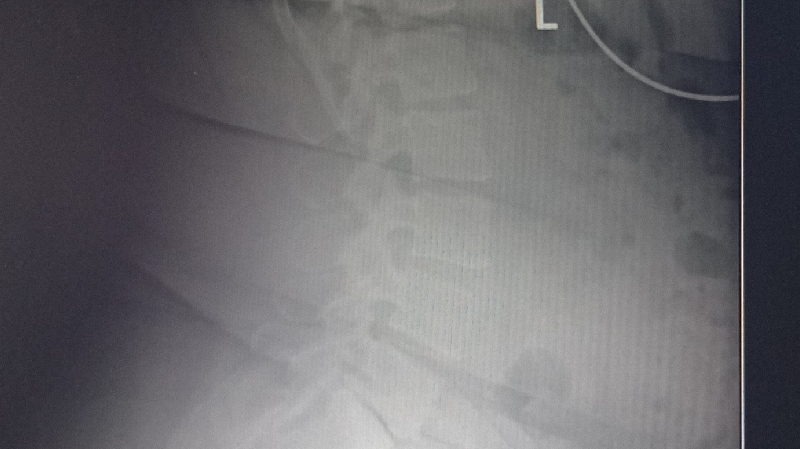

Finding out that my spine was disaligned and crooked and has spaces in my soiyne where there shouldn't be i will be out of work for a while to eliminate further damage keep me and mine in your prayers we appreciate any help